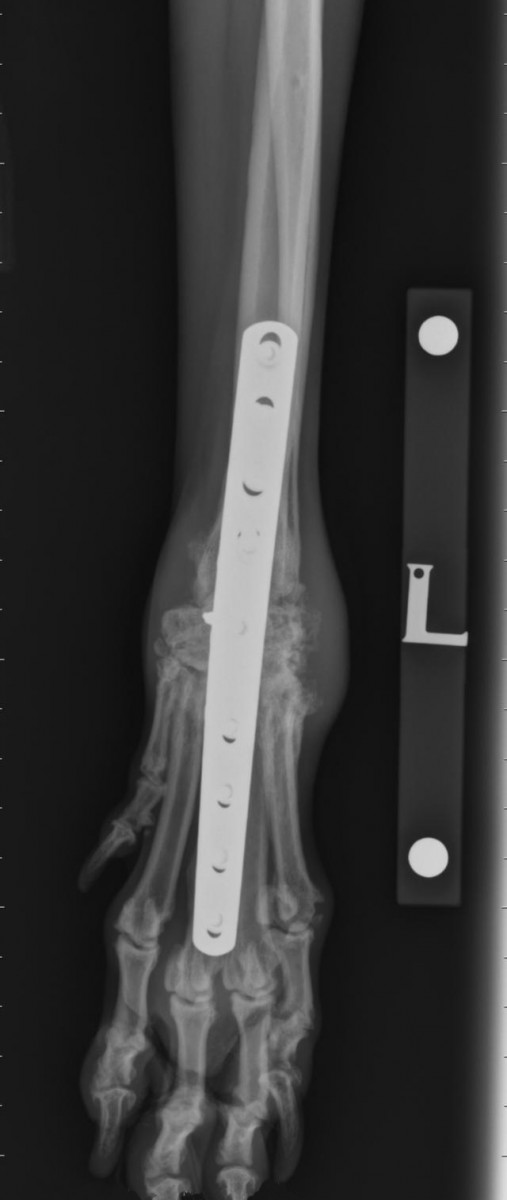

From www.frontiersin.org

Frontiers Implant removal rate after partial carpal arthrodesis in Dog Carpal Hyperextension Surgery Cost Can carpal hyperextension be treated? Additional fees may be charged for additional hospitalisation, further investigations and additional procedures if necessary. Warning signs of this condition include lameness, swelling of the carpus and sinking of the paw to the ground during. In puppies, the hyperextension is due to the looseness of the carpal flexor tendons associated with poor muscle tone. It. Dog Carpal Hyperextension Surgery Cost.